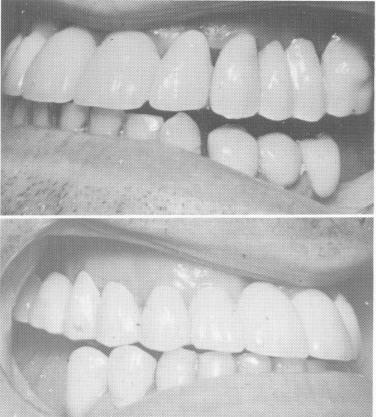

Fig. 15-26. The completed maxillary prosthesis included two posterior quadrants constructed of gold occlusal acrylic veneers and the anterior quadrant, which consisted of porcelain fused to metal. The posterior quadrants engaged with the anterior quadrant with gold dovetail interlocks. The interocclusal space between the new bridgework and the old lower restorations will then be closed by lengthening the lower restorations.

5 Maxillary prosthesis with gold acrylic veneer, porcelain fused to metal